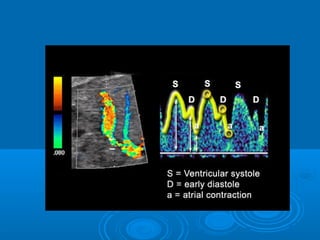

DV SPECTRAL WF:

 ‘M’ Pattern

High velocity , turbulent, forward

Normal ductus venosus spectra as a function of gestational

age. With advancing gestational age, the absolute flow

velocity increases while pulsatility declines.

DV – imp. event, forward flow

during atrial contraction